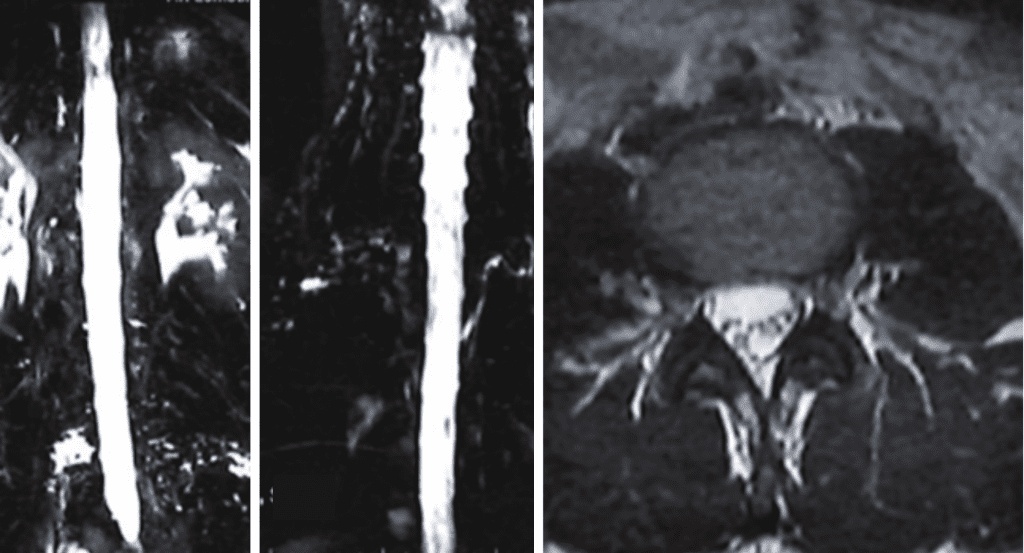

Imaging and other provocative diagnostic test showed the associated problems of Cranial Cervical Instability, incidental thoracic syringomyelia, Hashimoto Thyroidistis, Polycystic Ovarian Syndrome, Nutcracker Syndrome, Postural Orthostatic Hypotension, and Hypo/Hyper intracranial Pressure with spontaneous CSF leaks.

Her symptoms of Intracranial hypotension have been challenging.

The thin Dura in patients with EDS can dehisce at any point. Other causes include on osteodiscophyte penetrating the Dura, or rupture of a spinal nerve root diverticulum. Recent appreciation of other mechanism of Spontaneous Intracranial Hypertension (SID) includes CSF-Venous Fistula.

High Volume Blood patches under X-ray guidance, with a very small needle, being careful not to puncture the dura is indicated. This usually give relief lasting days to months. It may well need to be repeated.

Injection of fibrin glue into the epidural space, has a much greater chance of healing the CSF leaks. However, it can also impair “normal” CSF dynamics in these abnormally compensated situations, leading to intracranial hypertension.

Spontaneous Intracranial Hypotension (SIH) associated with EDS is often a complex disease. I am thankful to be part of a strong team that can address the plethora of problems these patients face.